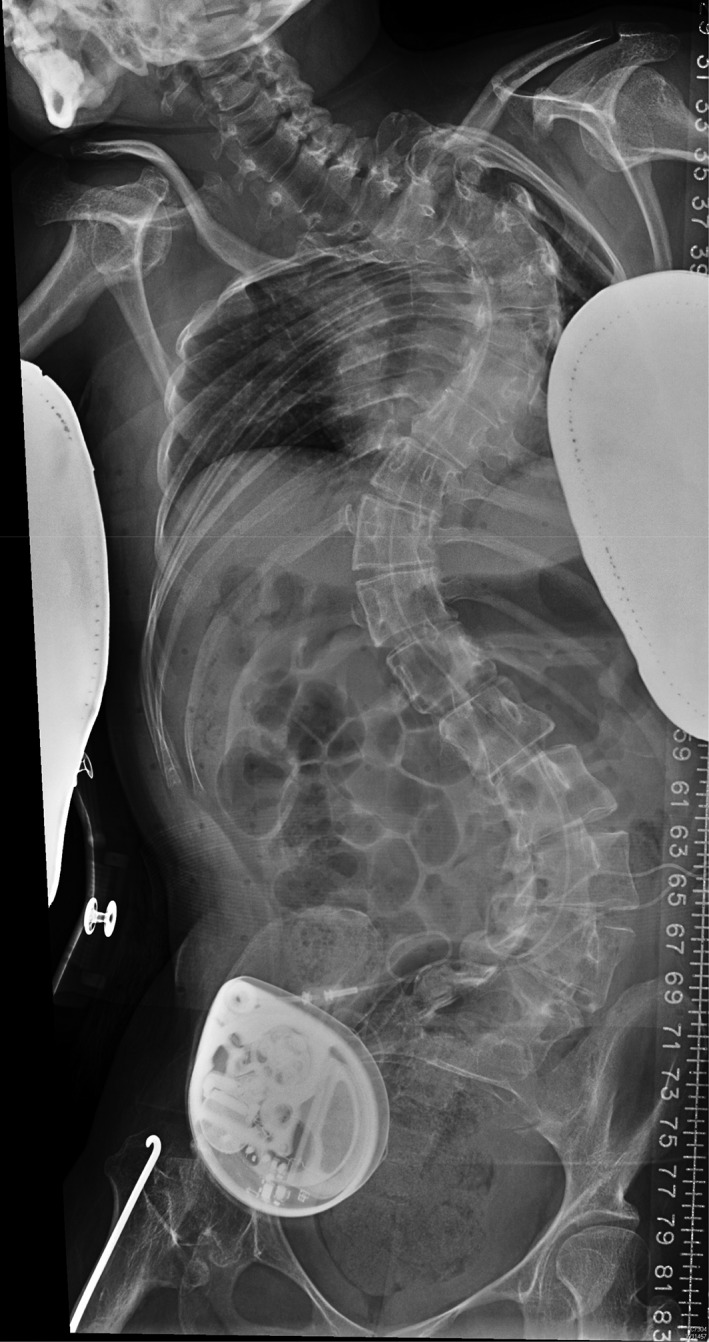

Figure 1.

X‐ray spine anterior–posterior view of a patient with severe spasticity treated with an intrathecal baclofen pump. Note the associated severe scoliosis. In view of the distortion, the X‐ray was reviewed for orientation of the pump at the right lower quadrant of the abdomen before needle puncture through the skin and subcutaneous tissue into the pump for refilling of baclofen into the reservoir.